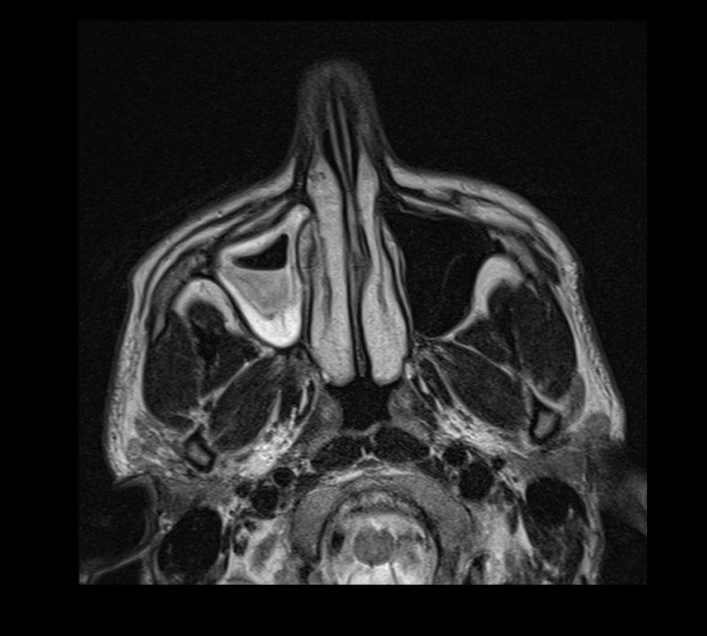

q se ve en imagen

A

nivel hidroaereo

Opacificacion

q se ve en tc

engrosamiento mucosa periferica

Niveles hidroaereos

Permite evaluar oclusion osteomeatal

Desviacion septum

Engrosamiento cornetes:rinitis